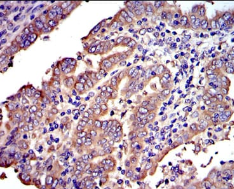

CRK Mouse Monoclonal antibody[3GPO1]

This gene encodes a member of an adapter protein family that binds to several tyrosine-phosphorylated proteins. The product of this gene has several SH2 and SH3 domains (src-homology domains) and is involved in several signaling pathways, recruiting cytoplasmic proteins in the vicinity of tyrosine kinase through SH2-phosphotyrosine interaction. The N-terminal SH2 domain of this protein functions as a positive regulator of transformation whereas the C-terminal SH3 domain functions as a negative regulator of transformation. Two alternative transcripts encoding different isoforms with distinct biological activity have been described.

Immunogen :   Purified recombinant fragment of human CRK expressed in E. Coli.

IHC    1/200 - 1/1000